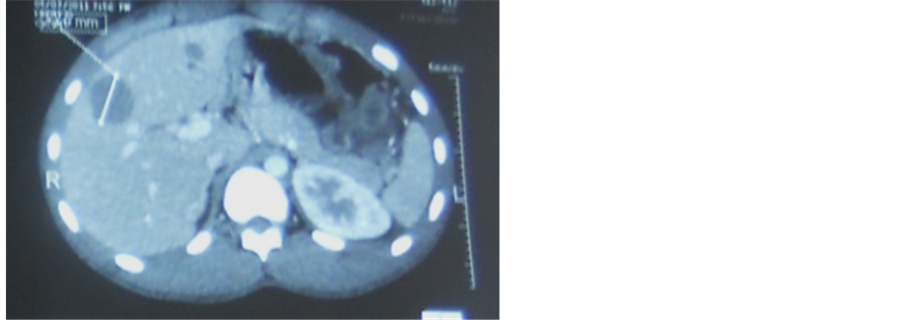

Radiography of the abdomen without preparation highlighted many water-scarce hydro levels. Testicular ultrasound highlighted an aspect of suspect heterogeneous testicle and bilateral testicular stones. A thoraco-abdominal-pelvic CT scan, there was the presence of 4 pulmonary nodules consistent with metastases, a bulky pelvic lymph node casting bridging the inter vesico-rectal area and responsible for extrinsic compression of the small intestine, lymph node inter casting aorto-caval and latero aortic and multiple hepatic secondary locations. Given this body of evidence, metastatic testicular tumor was raised (Figure 1 and Figure 2).

Figure 2. Liver met a stases.